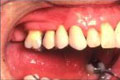

Before crowns After Crowns

Img9 Img10

Gaps before crowns Closed with crowns

Img11 Img12